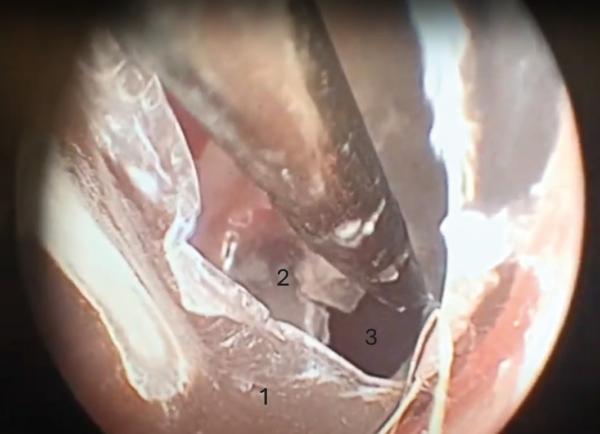

Miringotomía

La miringotomía es la incisión quirúrgica de la membrana timpánica, que permite acceder al oído medio para la toma de muestras, el lavado y la aplicación de terapia tópica (imagen 6). Esta técnica está indicada siempre que exista evidencia clínica de otitis media, anomalías de la membrana timpánica o hallazgos anormales en las imágenes diagnósticas (TC, RMN) del oído medio. Se deben recolectar muestras para investigación citológica y cultivo, y posteriormente limpiar y secar el oído externo. Este procedimiento debe realizarse bajo anestesia general inhalatoria y con un videotoscopio de fibra óptica para mejorar la visualización y reducir el riesgo de complicaciones. La incisión de la miringotomía debe realizarse en el cuadrante caudoventral de la membrana timpánica (pars tensa) utilizando una sonda urinaria de tamaño adecuado para recolectar muestras e irrigar la cavidad del oído medio.

En el caso de los pacientes felinos es posible el acceso al compartimento ventromedial de la bulla timpánica, tras la miringotomía y fenestración del septo de la bulla (imagen 7).

Se debe tener un conocimiento profundo de la anatomía, la técnica y la posible ototoxicidad de la terapia tópica para minimizar el riesgo de complicaciones neurológicas y de otro tipo. La membrana timpánica suele cicatrizar en un plazo de 35 días si se mantiene libre de infecciones.